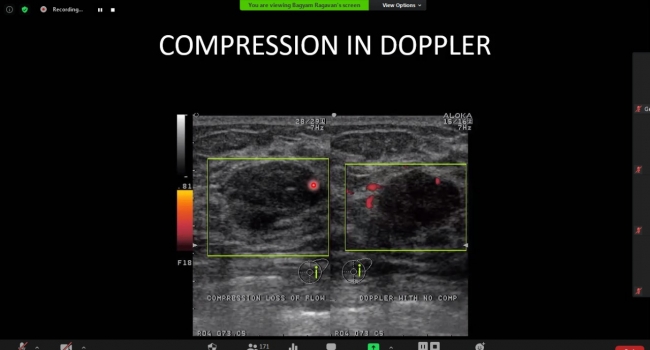

Session 2 breast ultrasound knobology & USG BI-RADS: Clinical webinar session was led by Dr Bagyam Raghavan & Mr. Debasis Manna to educate the audience with valuable information about breast imaging. The session was attended by more than 170 attendees including leading Breast Radiologists & Technologists from across South & South East Asia. Session 2 breast ultrasound knobology & USG BI-RADS: Clinical webinar session was led by Dr Bagyam Raghavan & Mr. Debasis Manna to educate the audience with valuable information about breast imaging. The session was attended by more than 170 attendees including leading Breast Radiologists & Technologists from across South & South East Asia.